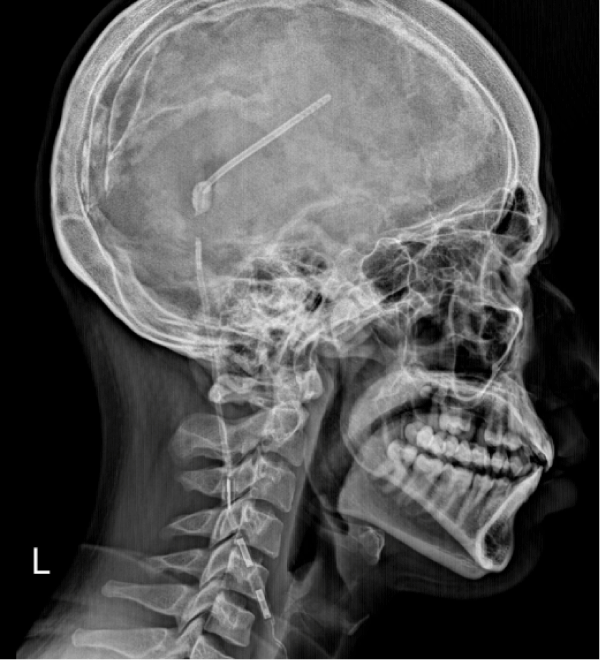

Further imaging, including a shunt series X-ray, demonstrated a disconnection of the VP shunt along the cervical tract (Figure 2), and most likely related to the recent cervical trauma.

Figure 2: Lateral skull X-ray (right profile) showing a disconnection of the shunt system. View Figure 2